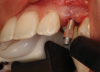

(38.) The opaqued titanium provisional abutment was gently tightened onto the implant.

Figure 38